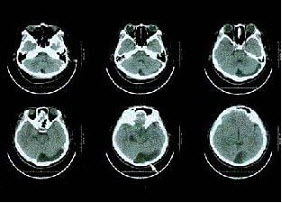

63、单项选择题

女性患者56岁,突发黑朦2h,无头疼及意识障碍,行99Tcm-ECD脑血流断层显像及CT扫描如图,诊断是()。

A.左侧额叶、顶叶脑梗死

B.左侧额叶、顶叶、颞叶TIA

C.交通性脑积水

D.左侧大脑半球癫痫

E.PD改变